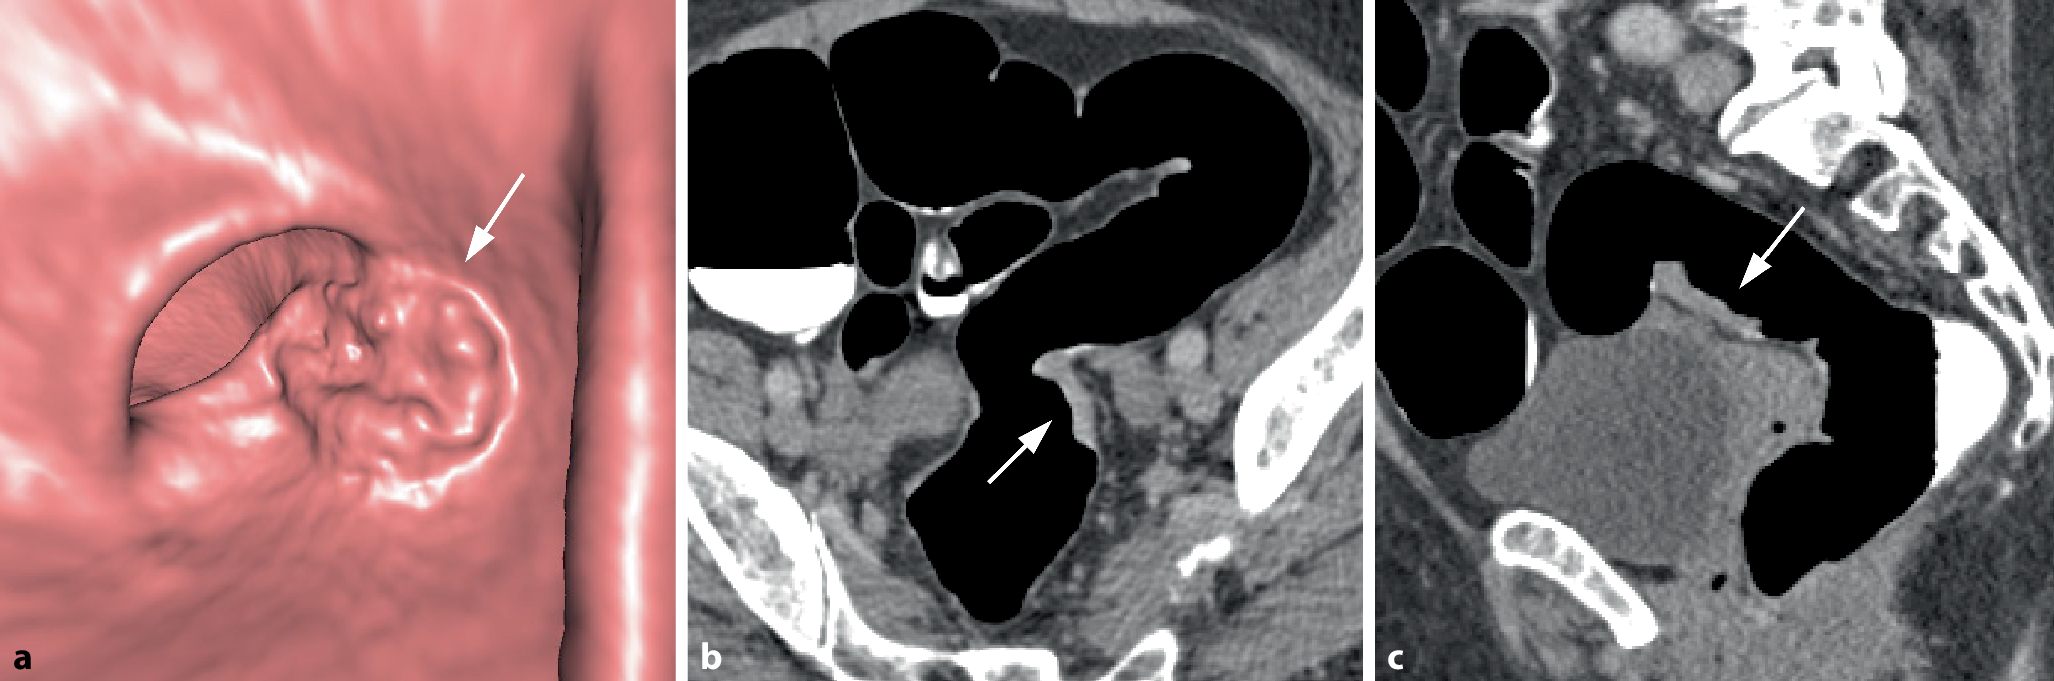

Bei semizirkulären Tumoren nimmt die tumoröse Wandverdickung nur einen unterschiedlich großen Anteil der Zirkumferenz eines Darmsegments ein (Abb. 3). Bei kleineren Tumoren kann sich dabei in der 3D-Darstellung ein Aspekt ergeben, der an einen Pferdesattel erinnert (Abb. 4).

Abb. 3

Semizirkuläres Karzinom im Colon sigmoideum. a Die endoluminale 3D-Ansicht und das korrespondierende parasagittale (b) und parakoronare 2D-Bild (c) zeigen die tumoröse Wandverbreiterung mit Schulterformation, die nur einen Teil der Dickdarmzirkumferenz betrifft (Pfeil). c Das parakoronare 2D-Bild zeigt die kurzstreckige Tumorlängsausdehnung und die homogene, weichteildichte Struktur (Pfeil)

Abb. 4

Sattelförmiges Karzinom im mittleren Rektum. a Die endoluminale 3D-Ansicht zeigt eine kleine sattelförmige Läsion im mittleren Rektum (Pfeil). b Das axiale 2D-Bild zeigt eine kurzstreckige semizirkuläre Wandverbreiterung mit Schulterbildung und weichteildichter Struktur (Pfeil)